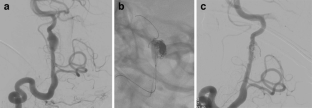

We report our experience with endovascular treatment (EVT) of circumferential and fusiform intracranial aneurysms by a reconstructive approach with self-expandable stents.

From April 2004 to May 2007, 13 patients were identified, of whom 12 were asymptomatic and 1 presented with a subarachnoid hemorrhage. Two patients with an aneurysm ≤2 mm were treated by stent-within-stent placement without coiling (group 1). In 11 patients with a larger aneurysm, stenting with subsequent coiling was performed (group 2). In this latter approach, a balloon was temporarily inflated within the stent to ensure safe coil delivery. All patients showed an excellent clinical outcome. Asymptomatic procedural complications occurred in three patients, two with cervical internal carotid artery dissection and one with retroperitoneal hematoma. In patients of group 1, the aneurysm had completely disappeared at 6 months. In patients of group 2, aneurysm occlusion was complete in three and incomplete in eight. Follow-up angiography in 12 patients showed four with further thrombosis, six with stable results, and two with minor recanalization.

Circumferential and fusiform intracranial aneurysms may be treated by a reconstructive endovascular approach with self-expandable stents. In small aneurysms, a stent-within-stent technique is effective, whereas stenting and subsequent coiling is indicated in larger aneurysms. This therapeutic protocol is associated with good clinical and anatomical results.